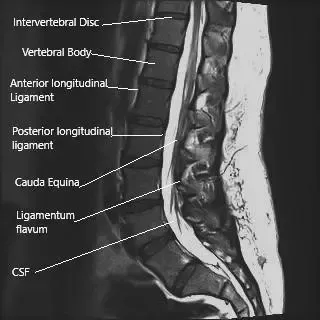

MRI of the lumbosacral spine in sagittal section.

The nerve may be compressed (pinched nerve) or irritated due to a herniated intervertebral disc, narrowing the neural canal due to spinal stenosis, or secondary to degenerative disc disease. The symptoms of sciatica occur due to the inflammation at the site of the compression/irritation. Inflammatory mediators are specific proteins released by certain cells at the site of aggravation.

The spinal cord ends at the level of lower L1/L2 vertebrae. The spinal cord continues below as a collection of spinal nerve roots that branch from their respective neural foramen. The spinal cord and the bunch of spinal nerves (cauda equina) are covered by a protective covering known as dura mater.

The epidural corticosteroid injections are aimed to be delivered just outside the dura mater (epidural space). The epidural space contains the exiting nerve roots, dural sac, blood vessels, and fat. The epidural corticosteroid injections provide a localized concentration of steroid.